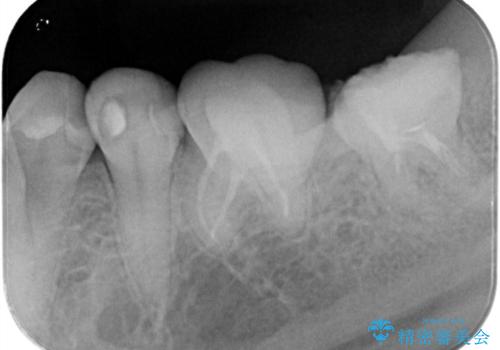

レントゲンや口腔内所見にて以下のような説明ののち、患者様が保存を希望されたため、当院では根管治療~オールセラミッククラウンにて修復処置を行いました。痛みも消えて、経過良好です。

根尖部に透過像を認め、①何もしないと今後の経過として痛みが増悪することや、腫脹を伴うことがある。

病気の原因は細菌であるため、細菌数を減らすための処置として一般的に②根管治療という選択肢がある。再根管治療の場合は病気が治るのは7割ぐらいであり、それでも治らない場合は意図的再植術を行い9割近くまで成功率を高めることができる。ただし、今回のケースでは根尖が湾曲しているため意図的再植時の破折リスクが高いため適応は難しい。また、根尖の病変が治ったとしても、歯周病、カリエス、脱離や破折リスクがあり治療後抜歯になる可能性もある。治らない可能性や治療したとしても抜歯になる可能性があることを考慮し、③抜歯の選択肢をとる場合もある。